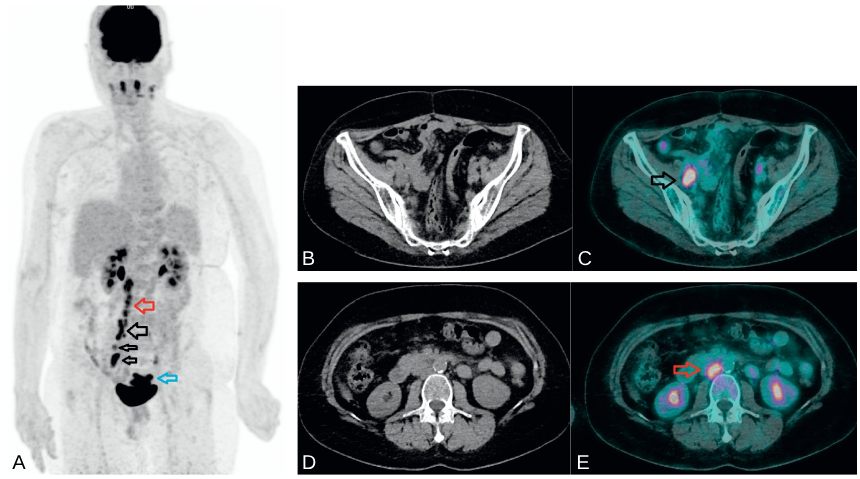

L’examen met en évidence des hyperfixations correspondant à des accumulations pathologiques de 18FDG en regard des atteintes lymphatiques et/ou métastatiques (figures 21.3 et 21.4).

Fig. 21.3 Bilan d’extension initial par TEP au 18FDG dans un cancer du col utérin de stade FIGO II.

Images MIP 3D (A) mettant en évidence un hypermétabolisme de la lésion du col utérin (flèche bleue) et de formations lymphatiques sous-diaphragmatiques. Images en coupes axiales, TDM à gauche (B et D) et TEP-TDM à droite (C et E), centrées sur ces formations lymphatiques hypermétaboliques iliaques externes droites (flèche noire) et lombo-aortiques (flèche rouge).

Source : CERF, CNEBMN, 2022.